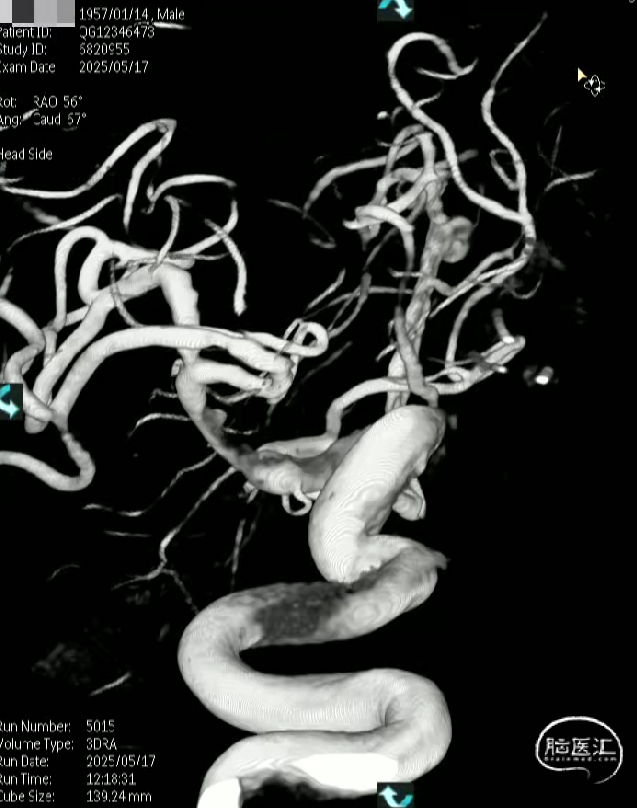

术前影像

· 患者三型弓,奇大脑前A3段动脉瘤,形态极不规则,血管入路极其迂曲

· 从大脑前动脉瘤起始段,有广泛伴有动脉粥样硬化的斑块

· 病变远端处于奇大脑前动脉双分叉位置,远端支架可着陆的空间较短,远端血管较细,且伴随斑块

术前测量

远端锚定点:1.5mm

瘤颈远端:1.53mm

瘤颈近段:2.4mm

动脉瘤瘤体直径:4.40mm